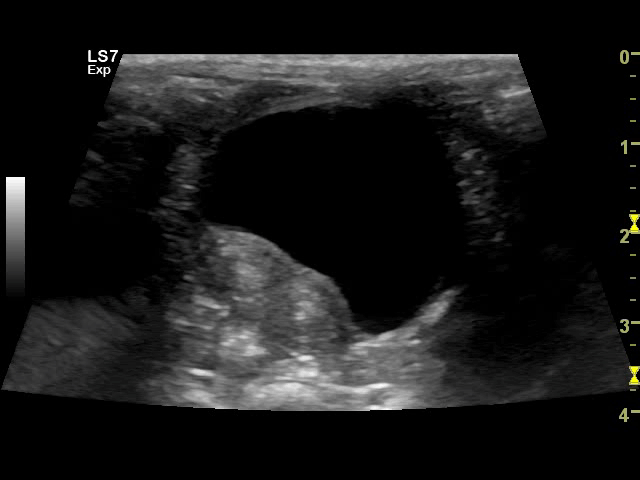

<em>An ultrasound showing a koala's healthy bladder and uterus. Good news, Willow is chlamydia free. </em><br />

“It turns out that koalas look remarkably like humans when you put them under an ultrasound,” says Mildren. “In koalas with chlamydia you see a thickening of the bladder wall, similar to what you see people when they have a urinary tract infection.”

A koala ultrasound in action. Willow is being checked for signs of chlamydia.

A recent study published in the journal of the Australian Veterinary Association supports the approach being used at Featherdale, suggesting that ultrasonography can be an effective tool for diagnosing the disease before the outward signs become apparent.